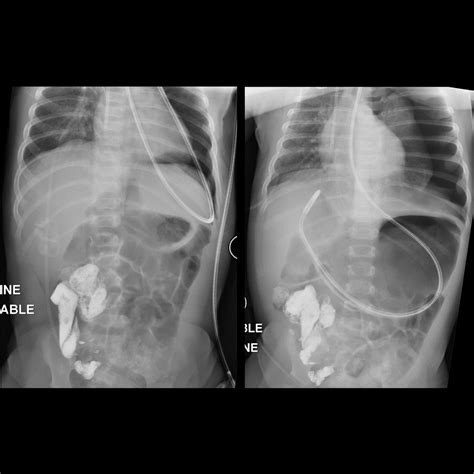

• Confirm the correct placement using auscultation or X-ray.

• Confirm the correct placement using X-ray.

• Secure the tube in place and confirm correct placement using X-ray.

• Confirm correct placement using X-ray.